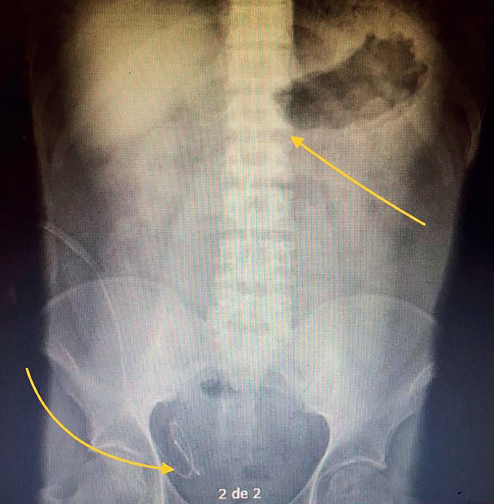

Solicitando valoración por el servicio de cirugía por dolor abdominal intenso generalizado, así como náusea y vómito e imposibilidad para evacuar de más de 24 horas. Identificando abdomen distendido, doloroso a la palpación media, ruidos peristálticos disminuidos, metálicos, sin datos de irritación peritoneal. Colocándosele sonda nasogástrica (obteniendo 50 cc de drenado en pozos de café). Radiológicamente se identifican en placa simple de abdomen niveles hidroaéreos en hueco pélvico, y la presencia de catéter Tenckhoff en adecuada posición, en cámara gástrica la sospecha de obstrucción a nivel de píloro (figura 1).

Figura 1 Rx simple de abdomen AP que demuestra niveles hidroaéreos en hueco pélvico, y la presencia de catéter Tenckhoff en adecuada posición, en cámara gástrica la sospecha de obstrucción a nivel de píloro.